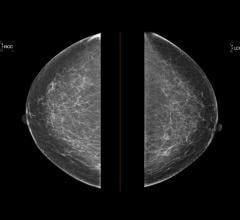

News | Breast Imaging | April 09, 2021

April 9, 2021 — 3-D mammography reduces the number of breast cancer cases diagnosed in the period between routine...

News | Breast Imaging | April 02, 2021

April 2, 2021 — iCAD, Inc. announced that ProFound AI for 2D Mammography might notably reduce the risk of interval...